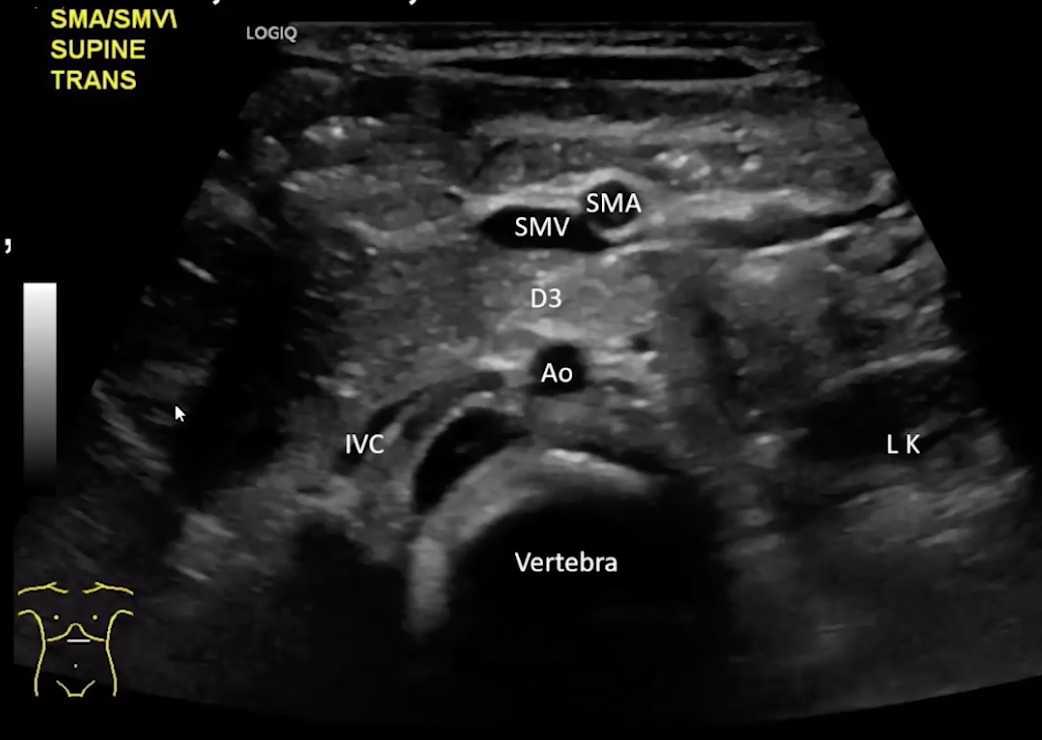

Malrotation

• Midgut = bowel supplied by the SMA

• Normal Anatomy

• D3 is retroperitoneal, should pass between SMA & aorta

• SMV on same side as portal vein

• SMA on same side as spleen

• Note that the SMA will have an echogenic halo around it and the SMV will not, important when there is concern for volvulus the SMV may be collapsed and you may just seen SMA which can be identified by that halo

• May be helpful to look for left renal vein crossing over midline to orient yourself too